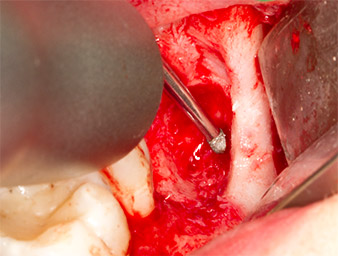

A continuación, se utilizó el accesorio P1 para retirar de una pieza el resto radicular de aproximadamente seis milímetros de longitud (figura 11).

El tejido inflamatorio periapical se retiró también con sumo cuidado utilizando un excavador manual. La figura 12 muestra el alvéolo vacío con el nervio alveolar inferior expuesto.

radicular extraído

Imagen 11: El resto radicular extraído medía más de 6 milímetros.

Nervus alveolaris inferior

Imagen 12: En la profundidad del alvéolo se distingue el nervio alveolar inferior.